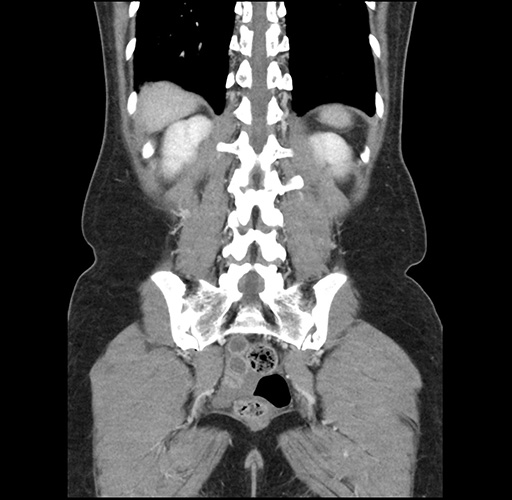

Imaging Analysis

Look through the patient's CT scan to identify any areas of concern for the necessary procedure.

Based on your CT findings, which issue(s) would give reason for "planned slowing down moment(s)" in this case?

Considering a standard left lateral sectionectomy procedure, what step(s) of the operation would you do differently in this case ?